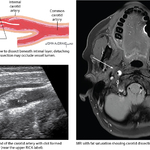

Arterial Dissection